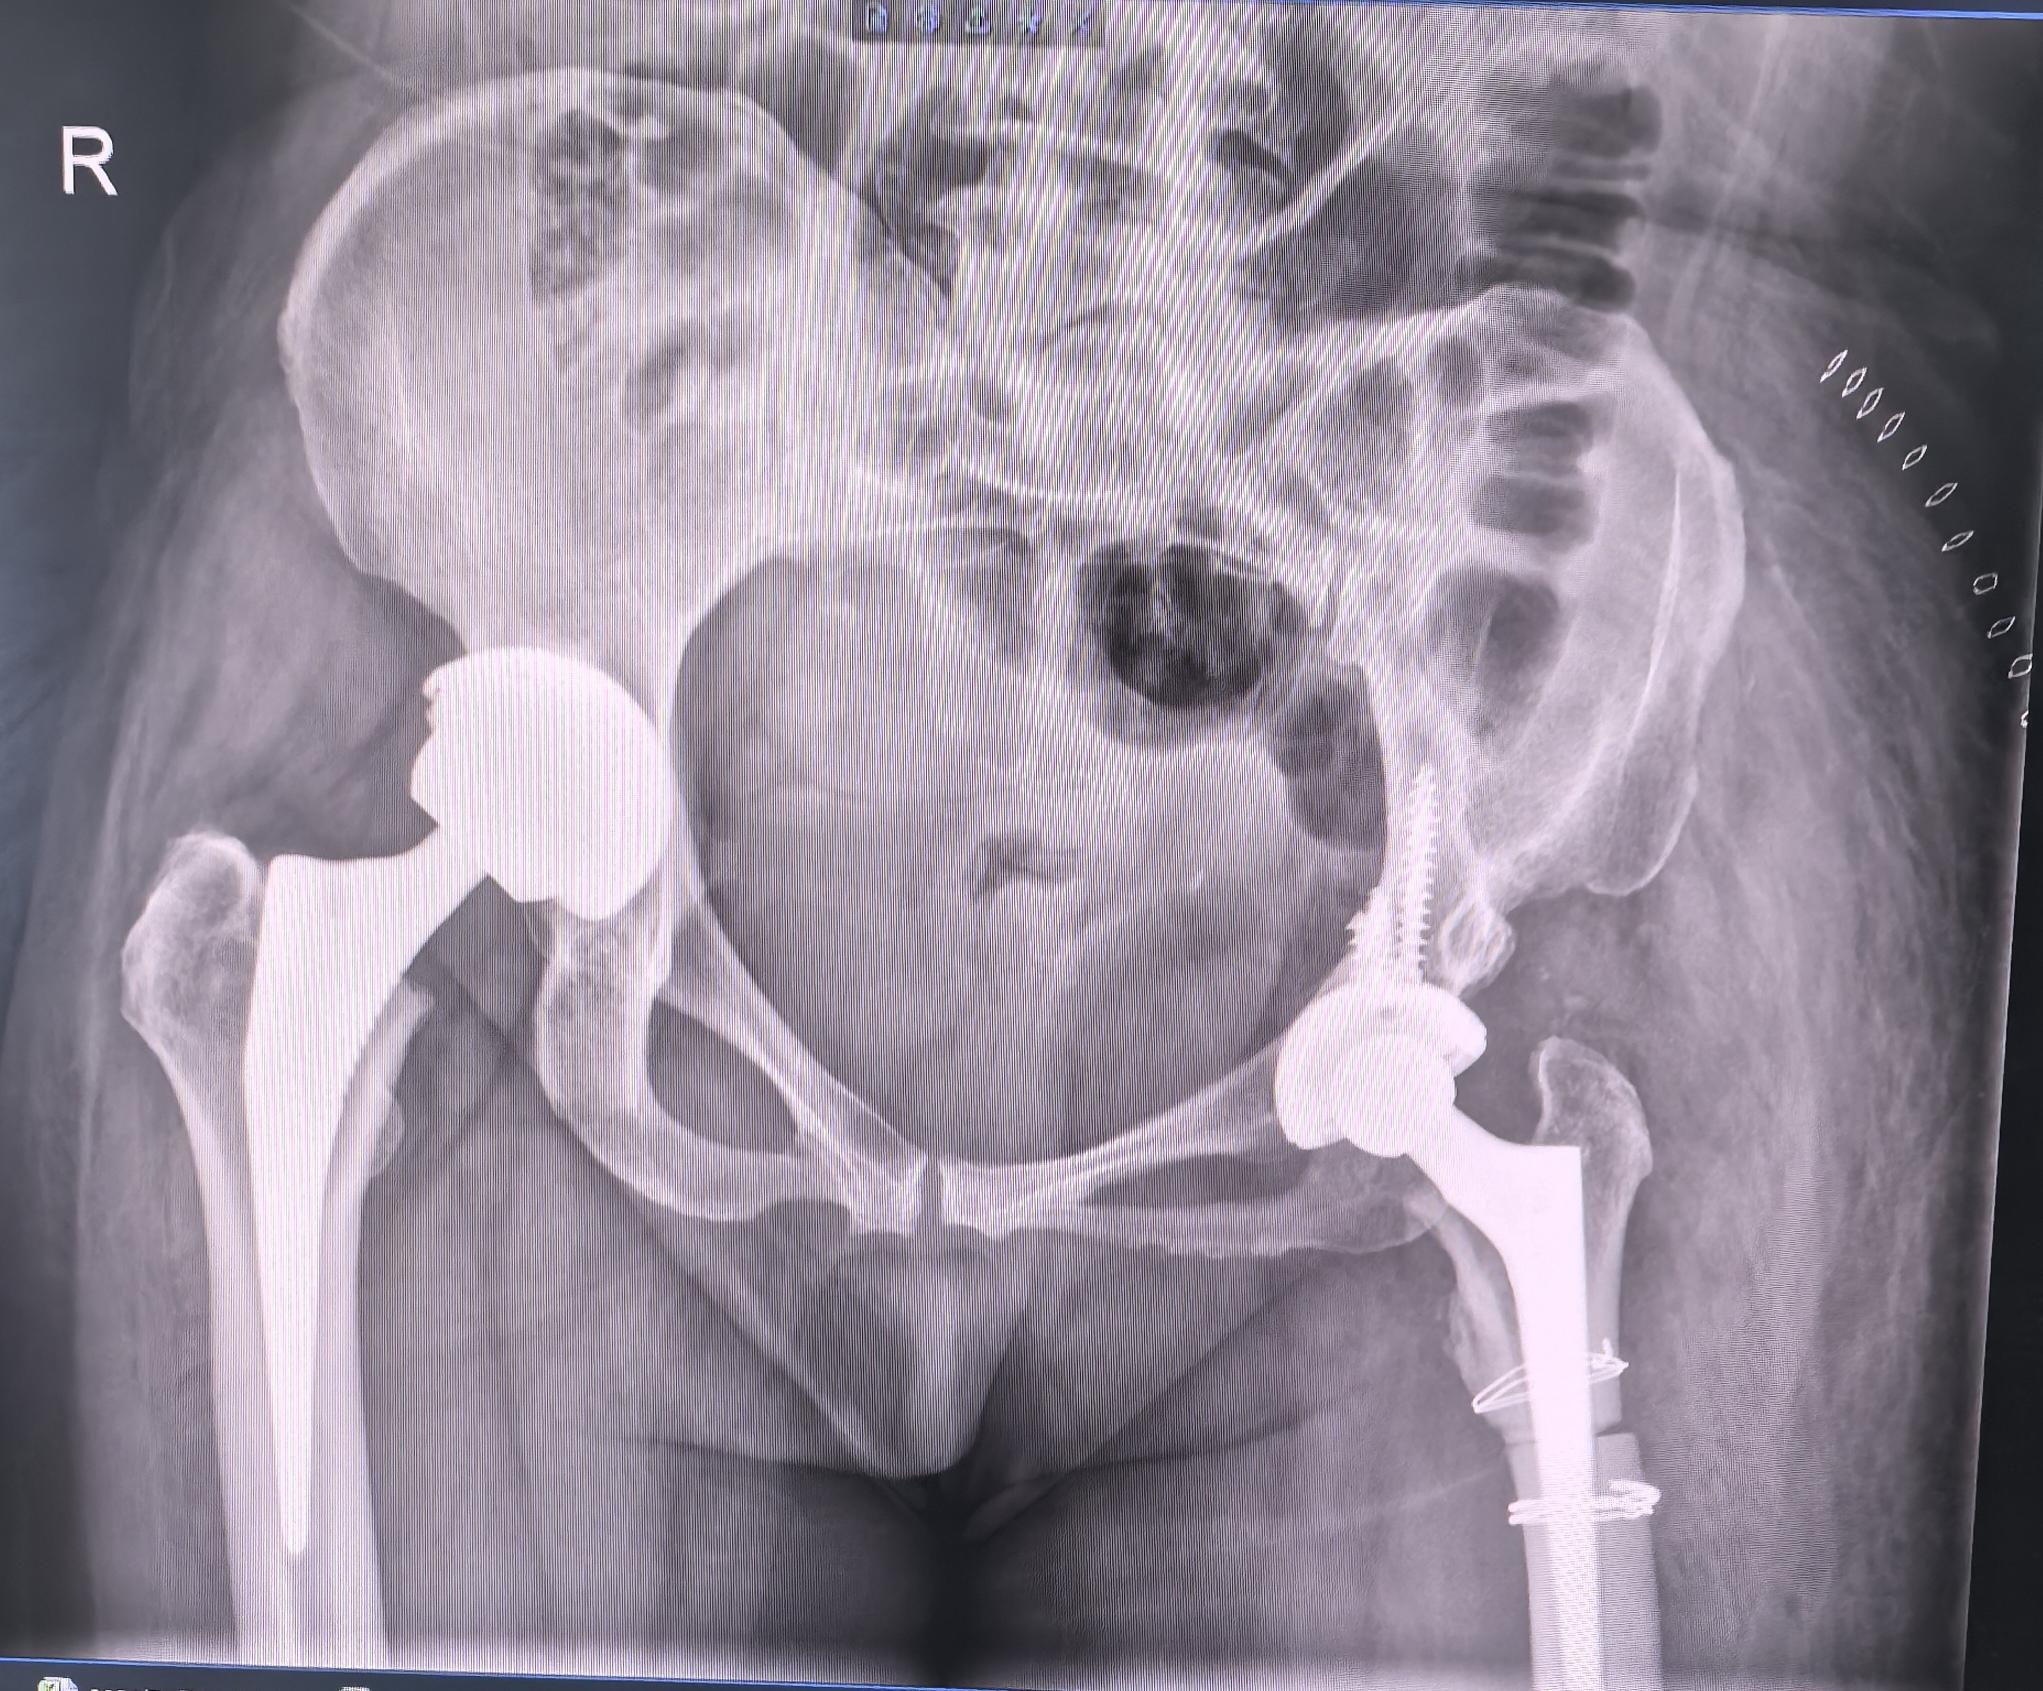

DDH先髋,高难度。DDH Crowe IV型,高难度手术,半个骨盆发育都不好,真臼25mm,髓腔直径5mm,术前患侧短4cm,术后等长,无神经症状,2天拄拐下床行走。愿每一位先髋患者都能得到有效的治疗,早日恢复正常生活🌹